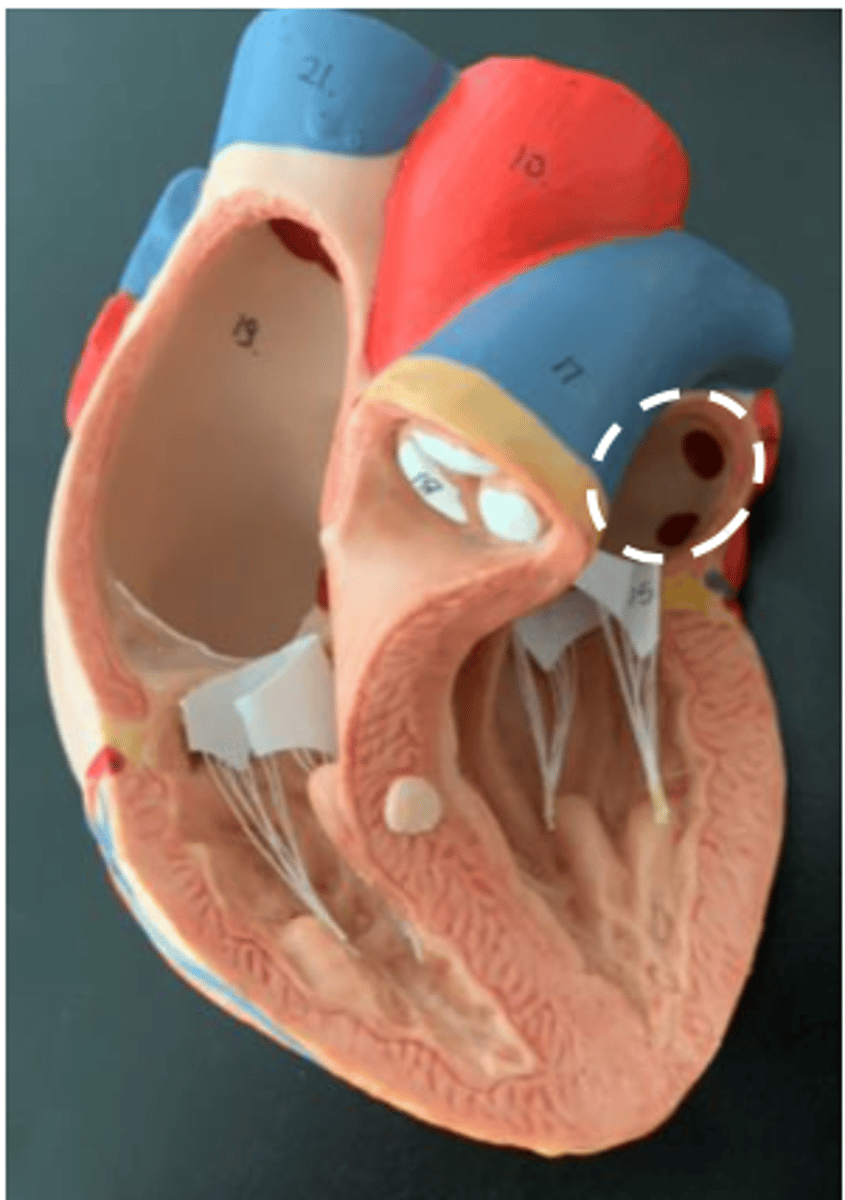

coronary sinus

(can only see on the real model)

<p>(can only see on the real model)</p>